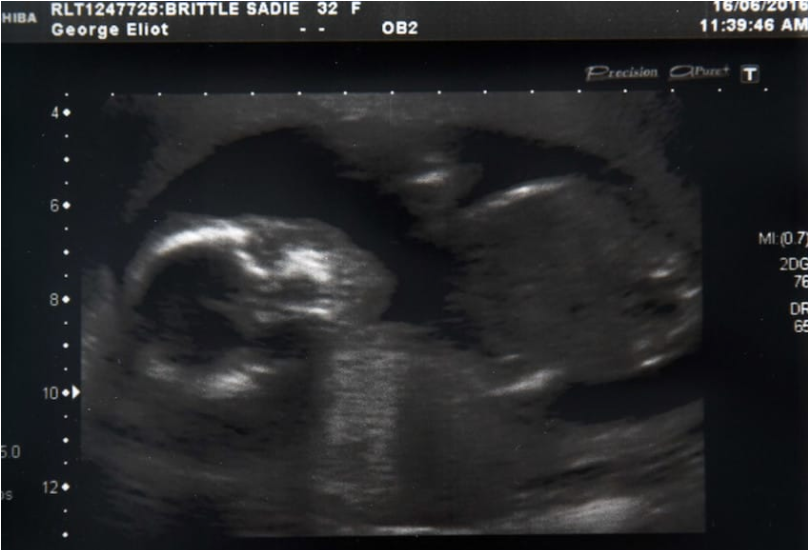

30 nov. 2016, 12:16ActualA pierdut sarcina și a fost devastată. Apoi, a observat că burta ei crește. Ce a aflat la medic: ȘOC